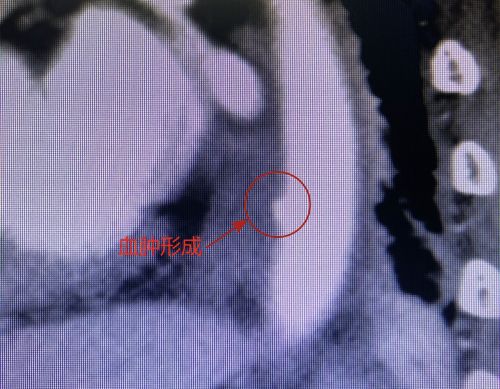

ct显示,鱼刺已经刺入胸主动脉。

好在血管没有被扎破,只是形成了血肿。